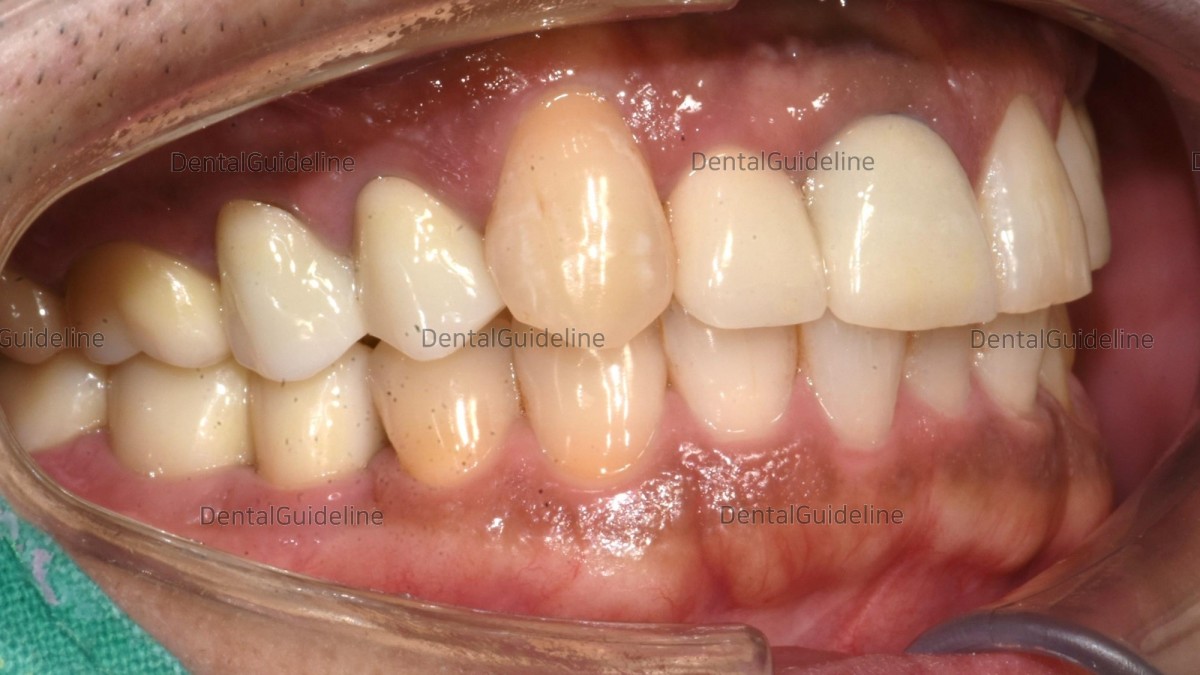

14. Intraoral photo after 7 years and 4 months. (lateral view)